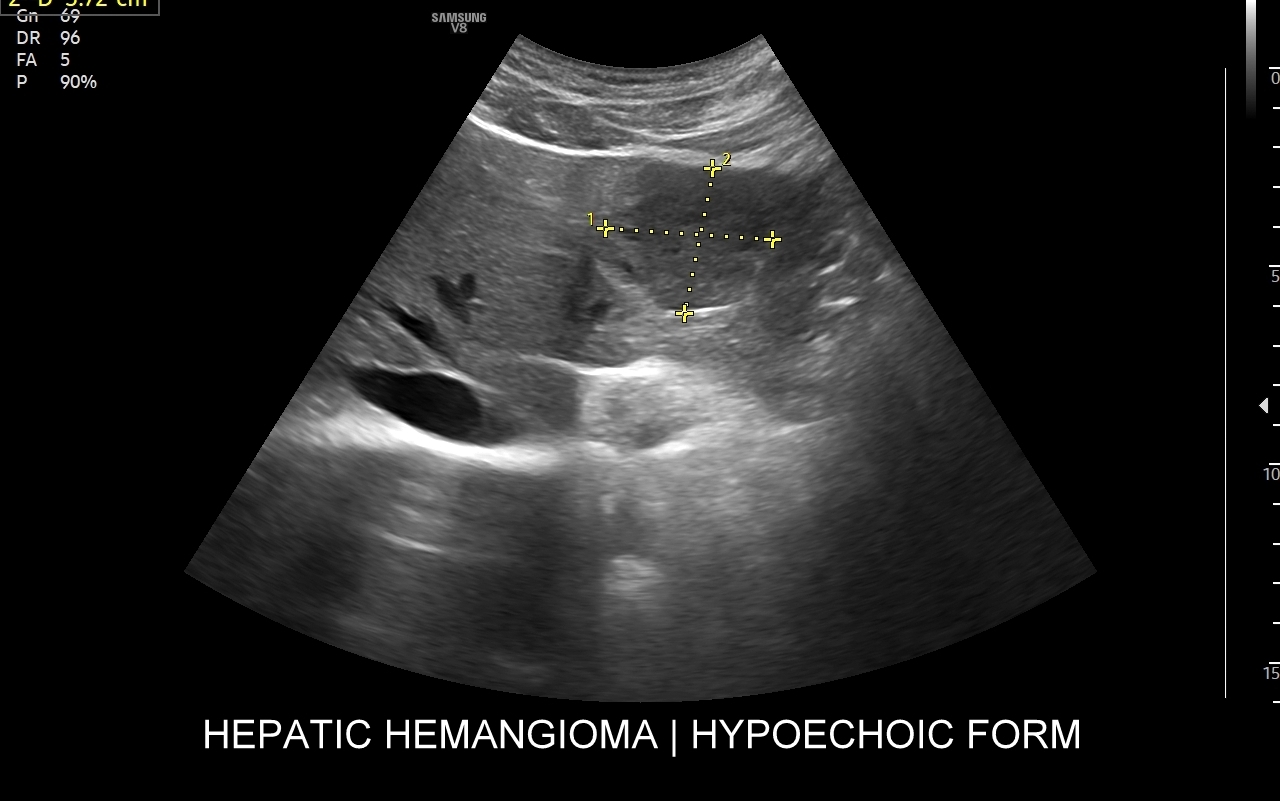

Badanie USG z kontrastem najczęściej wykorzystuje się do oceny zmian ogniskowych w wątrobie, potocznie nazywanych guzami wątroby, z których wiele ma na tyle specyficzny obraz mikrounaczynienia w obrazowaniu CEUS, że możliwe jest uniknięcie konieczności badania obciążającymi metodami TK lub MRI. Badanie CEUS w przeważającej większości pozwala odpowiedzieć, czy zmiana ogniskowa wątroby ma cechy złośliwe czy łagodne. Dodatkowo CEUS jest pomocny do wykrywania przerzutów do wątroby pochodzących z nowotworów w innej lokalizacji. W przypadku przerzutów o wielkości mniejszej niż 1 cm CEUS ma większą czułość aniżeli badanie TK.

Narządem, w którego diagnostyce najczęściej wykorzystuje się CEUS, jest wątroba; w dalszej kolejności nerki, trzustka, protezy naczyniowe aorty, drogi żółciowe oraz inne narządy wewnętrzne.